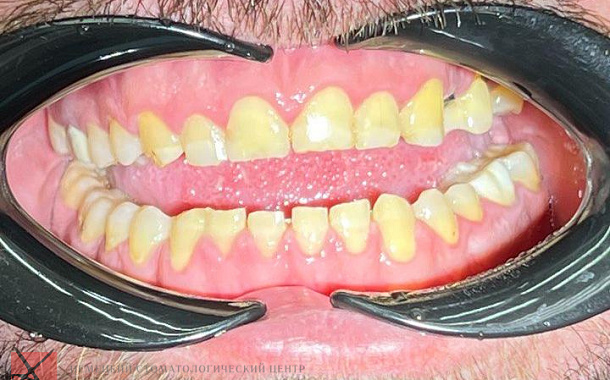

- Точное планирование: Детальные 3D-модели позволяют нашим специалистам тщательно спланировать каждый этап лечения, учитывая все анатомические особенности пациента.

- Визуализация результатов: Пациенты могут увидеть предполагаемый результат лечения еще до его начала, что помогает в принятии информированных решений.

- Минимизация погрешностей: Высокая точность сканирования снижает риск ошибок при изготовлении протезов и реставраций.